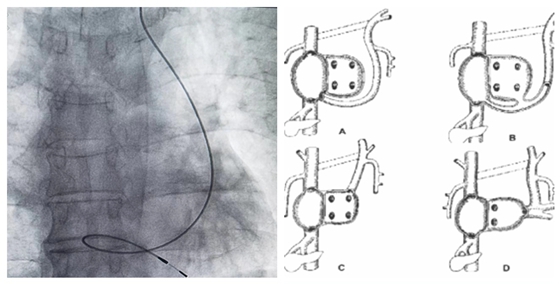

今年70岁的肖爷爷,最近一年时间内开始反复出现胸闷、心悸且有黑蒙,起初没有重视,但最近两月症状有所加重,就立即去当地医院就诊,最终确定是“病态窦房结综合征”,在当地医院进行永久起搏器植入发现,患者存在永存左上腔静脉,导致手术未能成功。患者及家属为求进一步治疗,遂转至湘雅常德医院心血管内科要求进行起搏器植入术。肖爷爷转入我院后,我院对老人进一步检查发现其确实存在永存左上腔静脉问题。经心血管内科主任彭道地、主任医师范爱德、副主任医师杨国栋、主治医师龚辉、医师彭双等多名医生多次讨论后得出结论:患者有行永久起搏器植入术适应症而无禁忌症。科主任彭道地手术前与患者家属充分沟通,说明本次手术难度很大。患者家属表示理解,最终确定手术于3月15日在导管室行永久起搏器植入术,术前行选择性左侧锁骨下静脉造影,可见左上腔静脉-冠状静脉窦显影,证实为A型永存左上腔静脉。做好充分术前准备后,决定从左侧锁骨下静脉穿刺,电极导线通过左锁骨下静脉-永存左上腔静脉-冠状静脉窦-右心房-三尖瓣-右室心尖部,成功植入单腔永久起搏器,术后安返病房。

图1 起搏器植入术后 图2 PLSVC分型

彭道地教授介绍,永存左上腔静脉(PLSVC)是最常见的体静脉畸形,在先天性心脏病中占2.8%~4.3%。正常人左锁骨下静脉与左颈总静脉汇合形成无名静脉,无名静脉则汇入上腔静脉,最后汇入右心房。PLSVC患者之无名静脉缺如或发育不良,左锁骨下静脉与左颈总静脉汇入PLSVC,PLSVC则经冠状静脉窦汇入右心房或开口于左心房。永存左上腔静脉可单独存在,但多数与其他先天性心脏病合并存在。90%PLSVC血流汇入右心房,与正常血液循环途径相似,故无临床表现。7%—10%左上腔静脉引流入左心房,由于大量的静脉血直接汇入左心系统,故临床常出现发绀。本次手术整体难度较大,但此类手术可以解决患者问题,更有益于患者恢复。